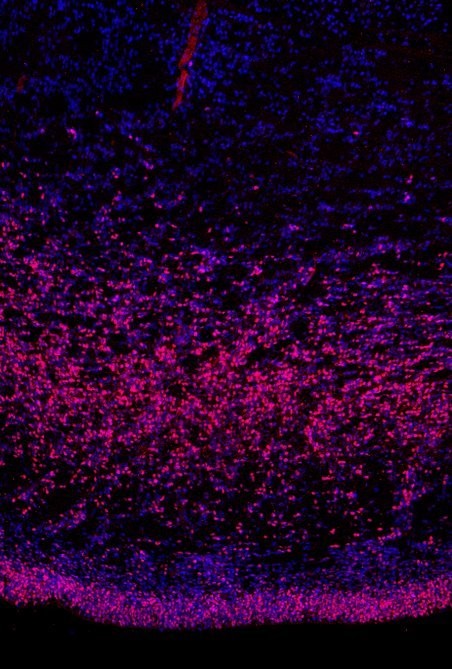

Dieses Bild ist im sich entwickelnden menschlichen Gehirn aufgenommen. Blau sind alle Zellkerne, rosa die neuralen Stammzellen dargestellt. Die untere Schicht Stammzellen haben alle Säugetiere. Die Schicht darüber zeigt die äußere Subventrikularzone mit neuen Stammzellen, die Wieland Huttners Labor 2010 entdeckt hat. [weniger]